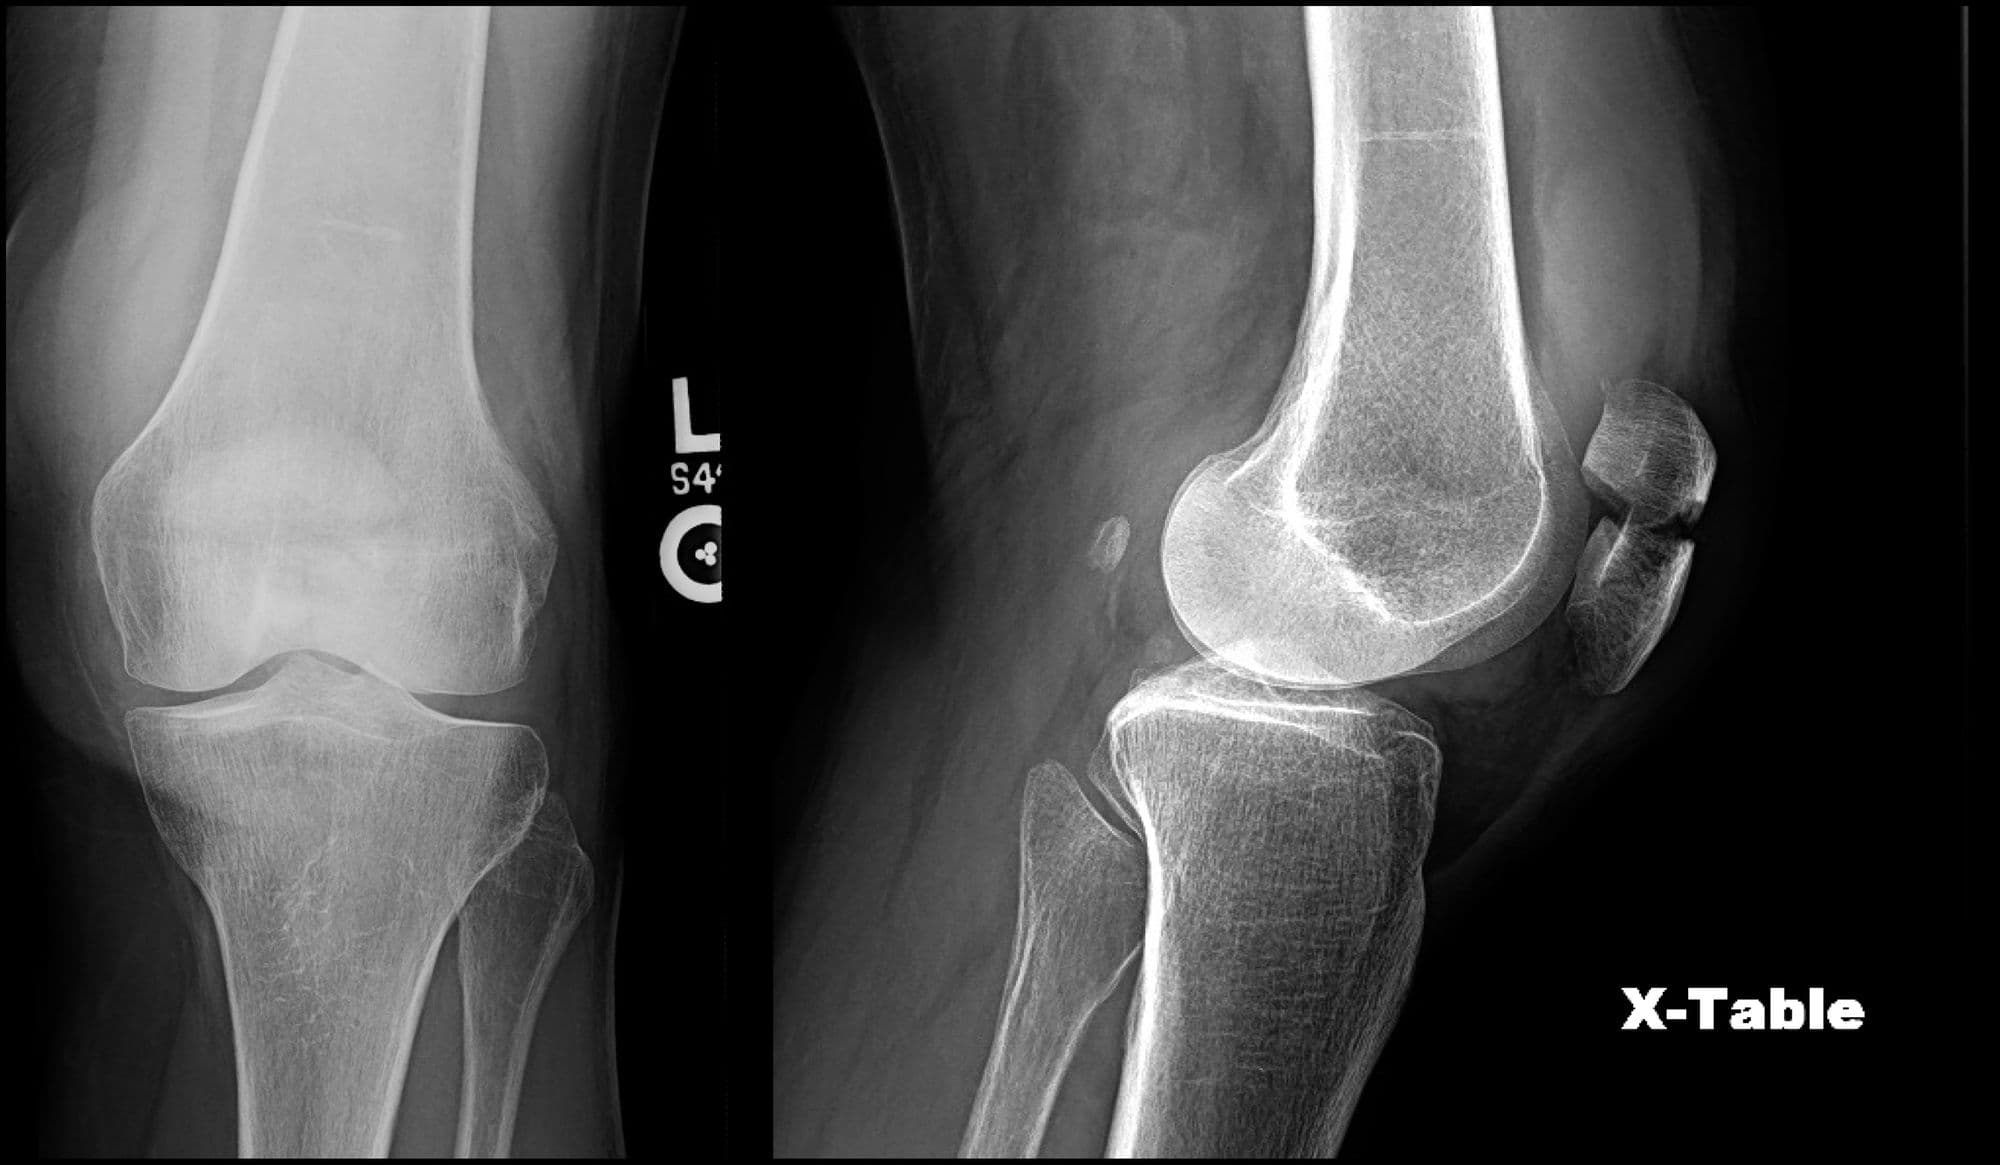

Pre-op